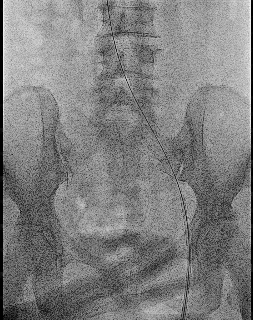

入路开通策略:左侧股总静脉顺穿。

2、导管导丝配合通过病变段后建立导丝路径,依次选择Atlas Gold 12*60mm、Atlas Gold 14*60mm对髂静脉逐段逐级扩张,扩张过程中见明显切迹。